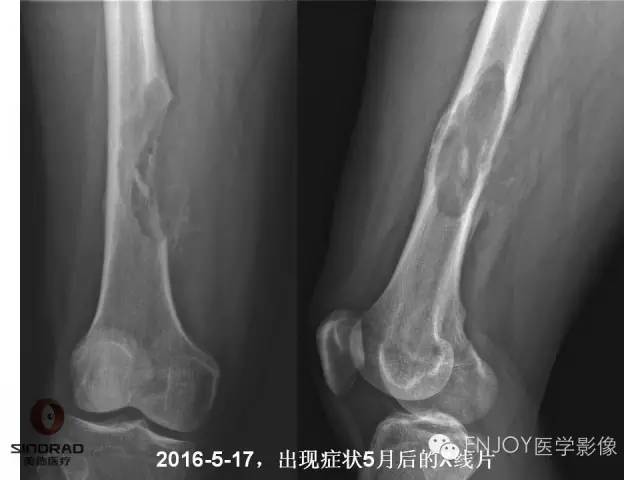

【病例】右侧股骨多形性肉瘤1例X线及MR影像表现

多形性肉瘤(以往称为:恶性纤维组织细胞瘤)